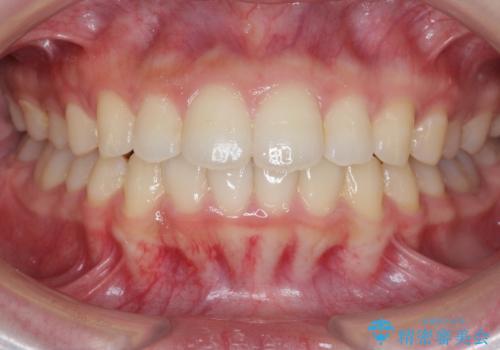

出っ歯を治すマウスピース矯正

- 出っ歯のように見える前歯の角度を治したい、と矯正治療を希望され来院されました。

抜歯をせずにマウスピース矯正システムインビザラインを用いてしっかりと前歯の角度を改善していきます。

前歯の角度だけでなく内側に倒れ込んでいた奥歯もしっかり起こすことで咬合関係も理想的に仕上げています。